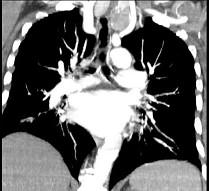

问题 40岁,女,发现颈部肿块,随吞咽上下移动,触之无搏动,咳嗽、气喘1周,请结合CT,检查选择最可能的诊断 ( )

选项 A.胸腺瘤 B.胸内甲状腺瘤 C.无名动脉瘤 D.无名动脉伸展扭曲 E.淋巴瘤

答案 B